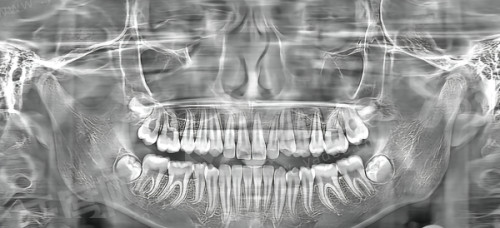

3、上海雅洁口腔定期组织医生参加国内外口腔学术交流,引进"数字化微创拔牙技术",通过CBCT三维成像定位,减少手术创伤,术后肿胀反应轻,修复期比传统拔牙缩短1-2天。